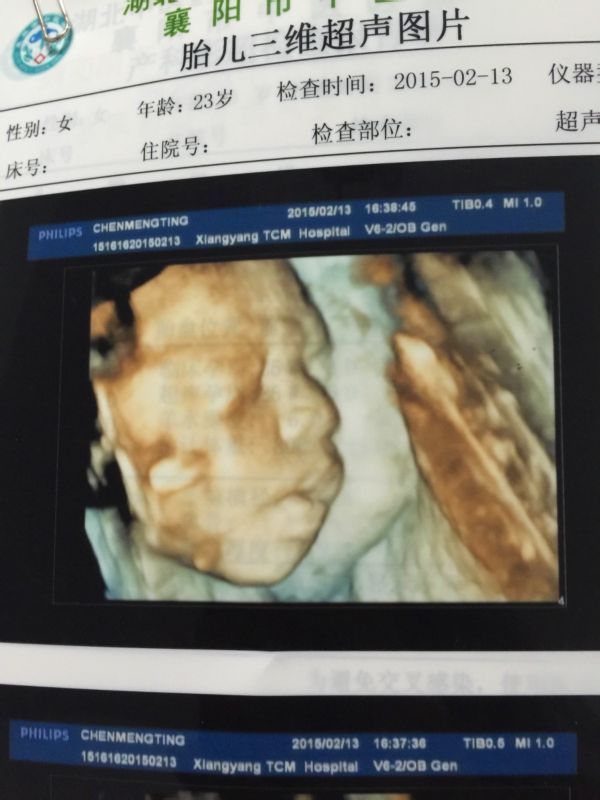

麻烦医生帮我看看我这是孕25周做的三围彩超,说胎儿左心室内可见一强回声光斑,是怎么回事啊?下面有单 子请医生帮我看看,谢谢啦!而且给宝宝拍的照片也好不清楚,不知道旁边是些什么东西! 点击展开 匿名用户 2015-02-13 18:19 为您推荐: 其他回答 你好,大部分心内强回声随着孕周的增加,逐渐消失,一小部分可能到出生后在彩超检中还能看见,心内强回声还可能与染色有关,建议结合唐筛结果,定期复查。 cn#BkkGGQBppp 2015-02-13 18:22 相关问题 宝宝三围彩超、左心室腔内可见一稍强回声光点是怎么回事呢、严重吗? 宝宝三围彩超、左心室腔内可见一稍强回声光点是怎么回事呢、严重吗? 彩超显示胎儿左心室见1 5X1 5MM强回声光斑,这是不是说胎儿心脏有问题???